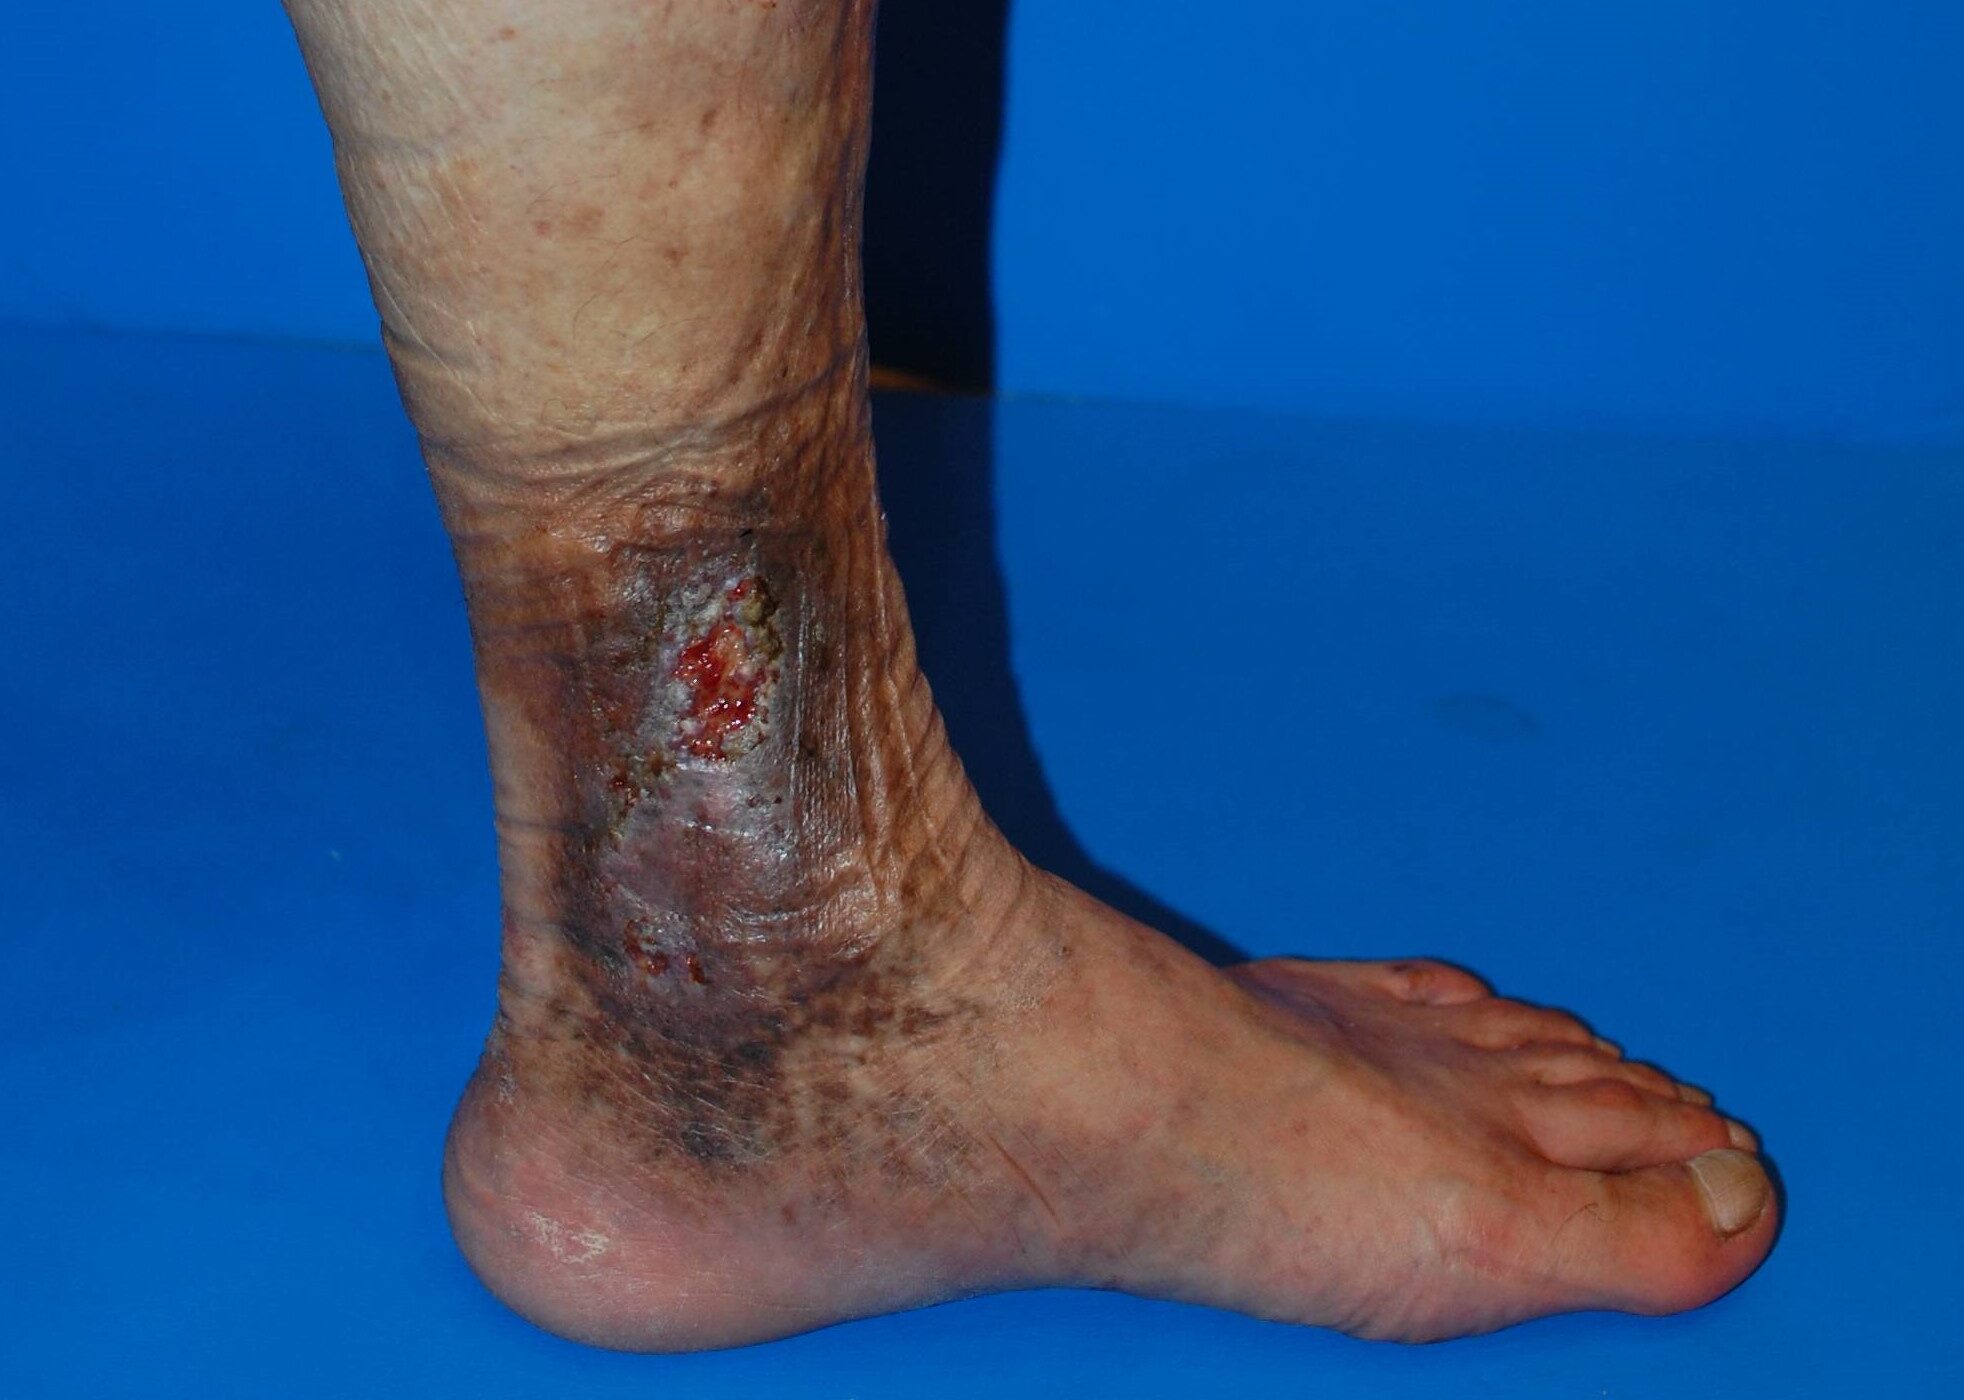

下肢静脈瘤 皮膚潰瘍

皮膚潰瘍とは、

皮膚がえぐれたように治らなくなる状態で、

- 長期間治らない

- 感染を起こしやすい

- 日常生活に大きな支障が出る

といった深刻な問題につながります。

下肢静脈瘤が原因の場合、皮膚だけを治療しても根本的な改善は難しいのが特徴です。